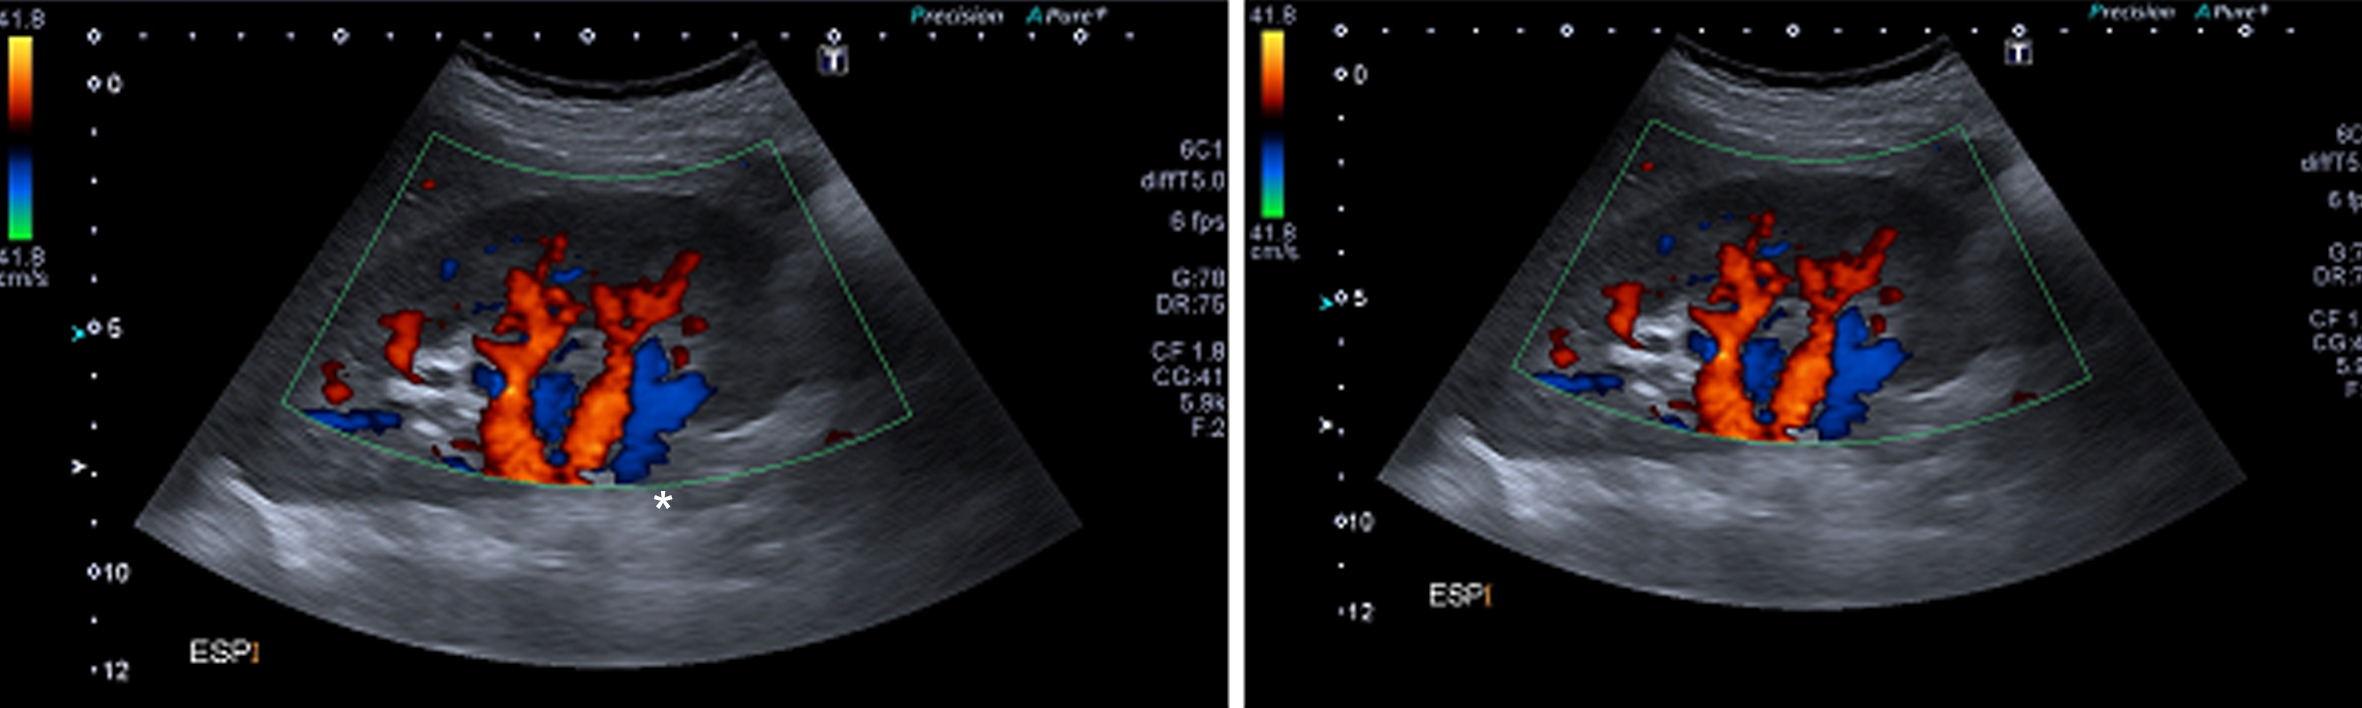

Figura 4

Ecografía Doppler, Cortes longitudinales. En espiración (izquierda) y en inspiración (derecha). (RD) Riñón derecho.

En espiración la arteria tiene un trayecto horizontal y velocidades de flujo normales (VPS de 122 cm/seg) (Fig. 5), siendo la vascularización intrarrenal de distribución habitual y con patrones de flujo normales. (Fig. 4)

Se comprueba una aorta abdominal ectásica en toda su extensión, con velocidades sisto-diastólicas habituales (velocidad picosistólica de 70 cm/seg.). Ambos riñones son de forma y tamaño habitual, con parénquima de espesor y ecogenicidad normal y buena diferenciación córtico-medular bilateralmente. No se ven alteraciones de las cavidades excretoras. Se realiza estudio dinámico de las arterias renales durante el ciclo respiratorio el cual demuestra que durante la inspiración el sector proximal de la arteria renal derecha se “verticaliza”, quedando paralela a la aorta abdominal, (Fig. 5), comprobándose además aumento de las velocidades sisto-diastólicas en este sector de la arteria, con velocidades picosistólicas (VPS) de 385 cm/seg en inspiración, comportándose desde el punto de vista hemodinámico como una estenosis significativa.

En esta fase del ciclo se observa íntimo contacto entre el sector proximal de la arteria renal derecha y la crura diafragmática ipsilateral, en concordancia con lo visto por angioTC.

Durante la inspiración es también evidente una disminución significativa de la vascularización del riñón derecho, con ondas de flujo de tipo “tardus et parvus” a nivel intrarrenal compatible con flujo post-obstructivo (postestenótico). (Fig. 6)

Ecografía Doppler (*) Crura diafragmática.